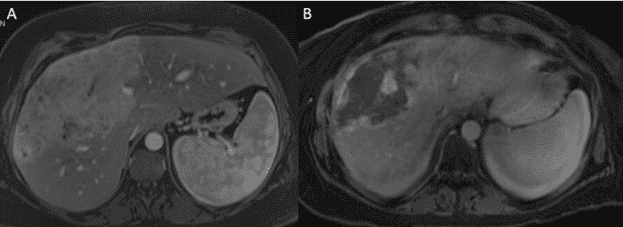

На відміну від пХАК та дХАК, які зазвичай супроводжуються такими симптомами обструкції жовчних шляхів, як жовтяниця, свербіж, потемніння сечі та світлий стілець, вХАК найчастіше виявляється у вигляді внутрішньопечінкового утворення як випадкова знахідка при виконанні КТ чи МРТ або під час проведення скринінгу у пацієнтів з цирозом печінки. Симптоми, про які повідомляють пацієнти, як правило, неспецифічні та можуть включати біль у животі, нудоту, втрату ваги або втомлюваність, ці ознаки пацієнти часто ігнорують, що і призводить до затримки діагностики. Діагноз можна запідозрити на етапі виявлення патологічних ознак на зображеннях КТ чи МРТ та підтвердити за допомогою гістологічної оцінки. Характерні особливості вХАК включають посилення артеріальної фази при магнітно-резонансній томографії (МРТ) чи комп’ютерній томографії (КТ) з контрастом без значного вимивання у венозній чи відстроченій фазі.

Зобр. 1. Типове зображення внутрішньопечінкової холангіокарциноми за допомогою комп’ютерної томографії на а) артеріальній та б) портальній венозній фазі зображення.